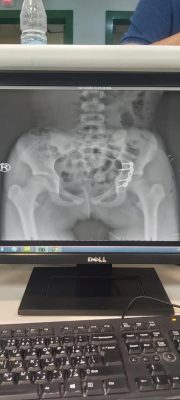

وقالت صحة نجران أن الفريق الطبي بمستشفى نجران العام استقبل الحالة عن طريق الطوارئ وكانت الطفلة تشكو من الآم شديدة مع عدم قدرتها على الحركة التامة وبعد إجراء الفحوسات السريرية والمخبرية والإشعاعية للطفلة اتضح أن لديها كسر في منطقة الحوض .

وقال استشاري جراحة العظام والاصابات واعادة الترميم والمشرف على الحالة انه تقرر على الفور إدخال الطفلة للعمليات لإجراء تدخل جراحي وإعادة ترميم منطقة الحوض التي تعرض لكسور شديدة بسبب إرتطام الطفلة بالأرض ، وتمت العملية بنجاح ونقلها لغرف التنويم لمتابعة الحالة مع المختصين في العلاج الطبيعي وتقديم الخدمات العلاجية والتأهيلية لها لحين استعادة قدرتها على المشي بالتدريج وعودة الحركة بشكلها الطبيعي إنشاء الله .